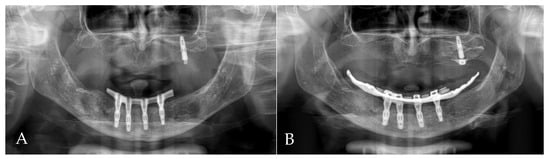

3.4. Results

- The present case report described the treatment process of a patient with periodontitis, including immediate implantation in the infected region, soft tissue augmentation using free gingival grafts and the ultimate placement of a bar-retained overdenture as the final restoration. After two years of observation, despite questionable hygiene, no symptoms of gingival inflammation were detected. The orthopantomogram did not show any bone resorption.